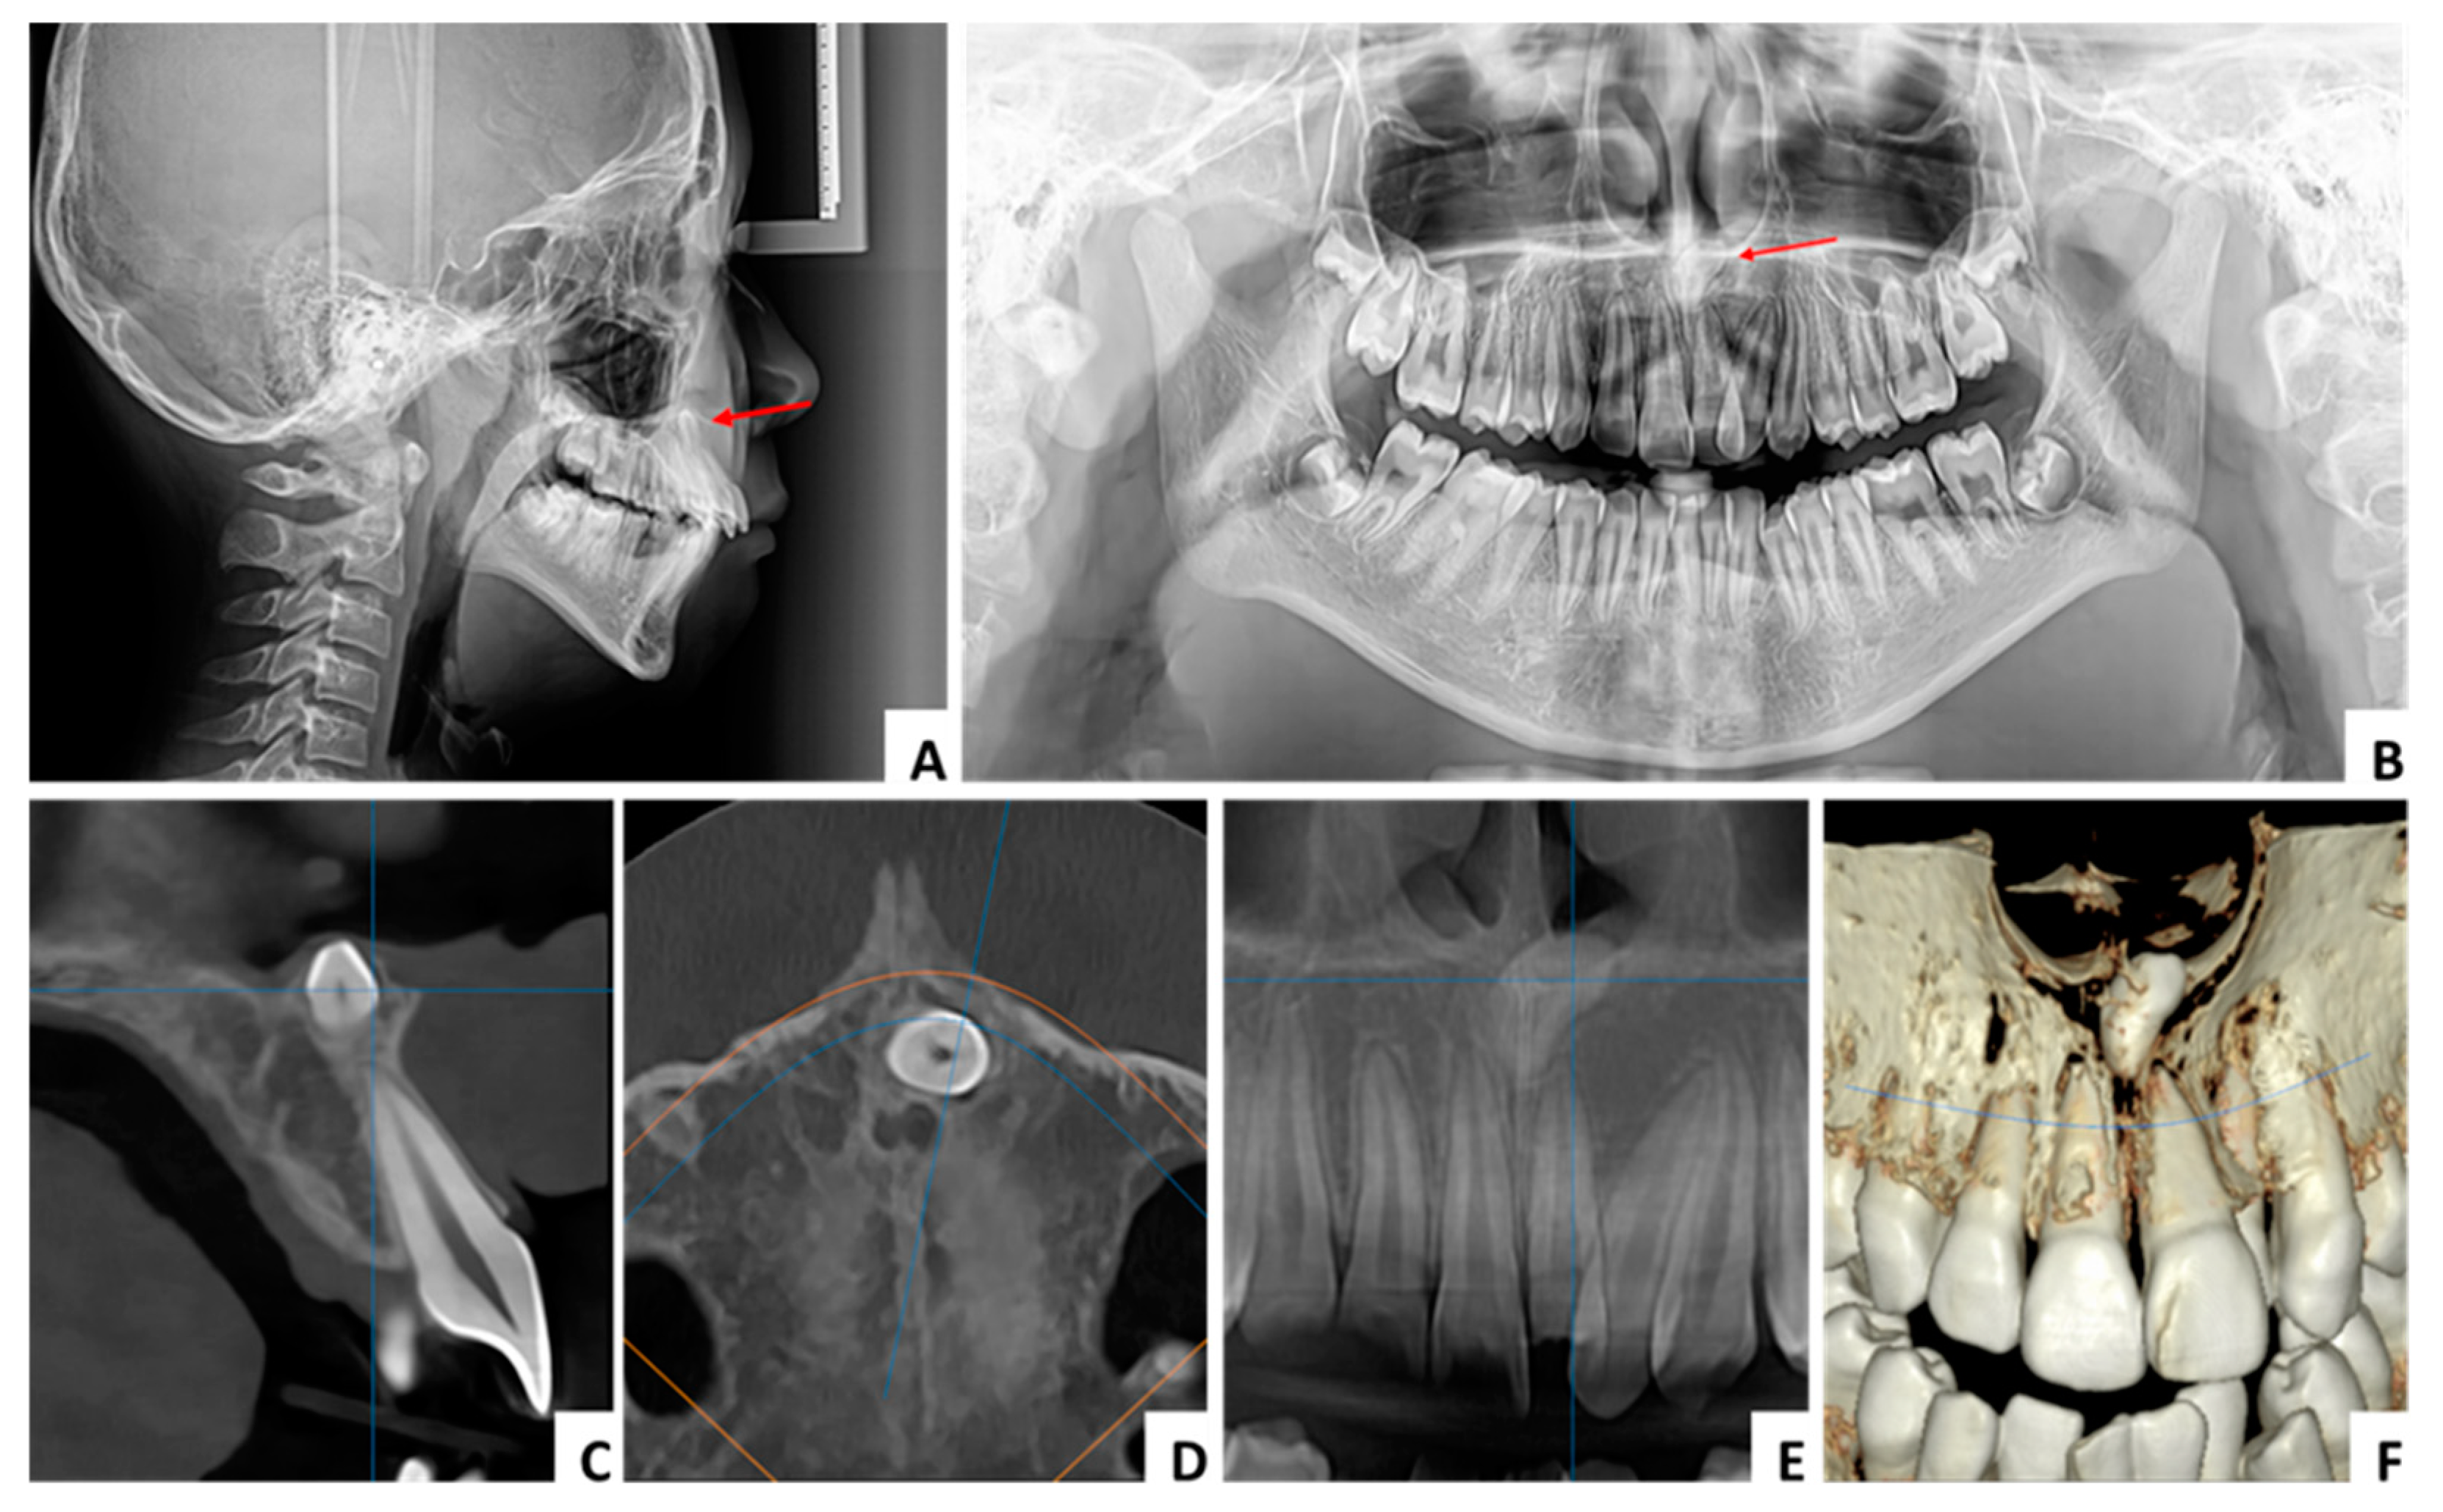

3.1. Case 1 (Figure 3, Figure 4 and Figure 5)

3.2. Case 2 (Figure 6, Figure 7 and Figure 8)

3.3. Case 3 (Figure 9, Figure 10 and Figure 11)

| Conventional radiography (OPG, occlusal, periapical, lateral cephalometric radiographs) | In the case of conventional 2D radiographs, mainly OPGs, the structures outside the focal area may be covered by other structures and cannot be visualized. Also, precise localization in relation to other anatomical elements or neighboring teeth will require the use of an additional occlusal radiograph. |

| CBCT | A 3D radiographic imaging method is an excellent method of evaluation and diagnosis. It has a fundamental role in the precise localization of the mesiodens and a connection with the neighboring anatomical structures and teeth. Thus, it has an important role in choosing the appropriate surgical procedure. |